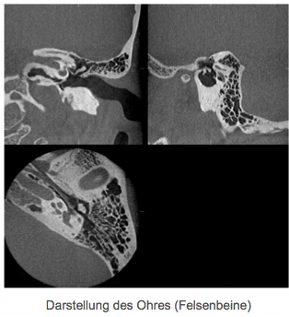

Die neue Technik ermöglicht eine exakte Planung und Realisierung der Behandlung im Kiefer-, Gesicht-, Zahn-, und Nasennebenhöhlenbereich sowie des Ohres. Even- tuelle Operationen, insbesondere Zahnim- plantationen sind dadurch schonender, sicherer und genauer bei reduzierter Eingriffs- dauer durchzuführen.